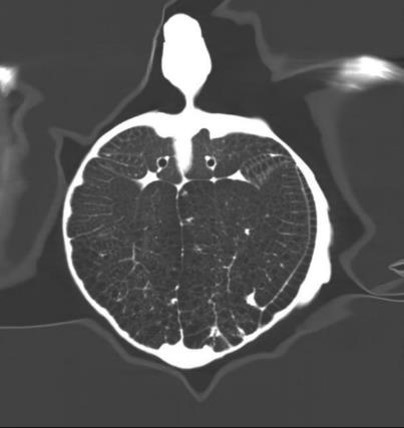

Uygulama Görüntüleri